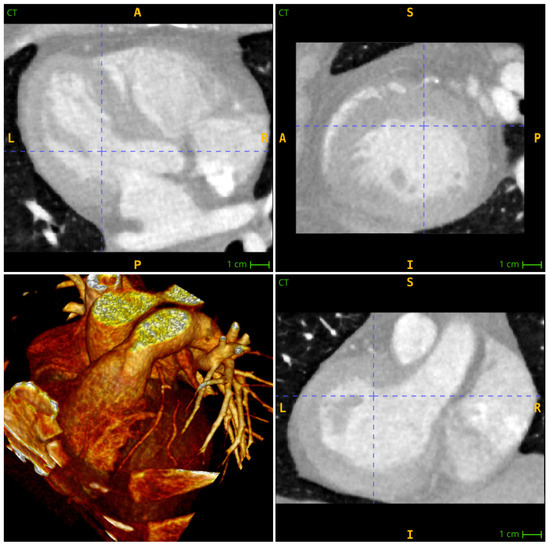

The initial stage of the process involves cropping the computed tomography (CT) images in order to include both the left and right ventricular chambers. Additionally, the ascending aortae are sectioned between the aortic valve and the aortic arch (Figure 1). This step is essential for enhancing the detection of the aorta on the CT image. It also minimizes the computational burden of subsequent segmentation algorithms. In certain instances, it may be preferable to resample the voxels and make them more cubic in shape.

Figure 1. A section of a CTP image showing high contrast in the ventricles, moderate intensity in the myocardial wall and low intensity in the surrounding tissue.